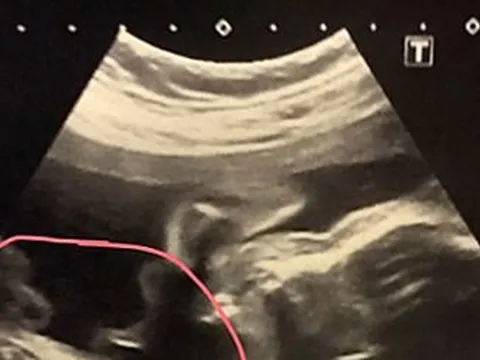

Đỉa dài 10 cm sống ký sinh trong mũi người bệnh. Ảnh: BVCC.

Qua khai thác tiền sử bệnh và thăm khám, nội soi, các bác sĩ chuyên khoa Tai – Mũi – Họng phát hiện một con đỉa sống đang ký sinh trong hốc mũi người bệnh. Dị vật sau đó đã được gắp ra an toàn. Con đỉa có chiều dài khoảng 10 cm. Sau can thiệp, tình trạng người bệnh ổn định, không ghi nhận biến chứng.